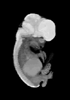

Carnegie Stage 22 (54 post-ovulatory days)

Most embryos at stage 22 are approximately 54 postovulatory days old and measure 25-27 mm in length. Distinguishing criteria for this stage include clear formation of the external ear, the hands begin to extend ventrally beyond the body wall, the fingers of one hand may overlap the fingers of the opposite hand, thickened eyelids just begin to cover the outer margins of the eye, and the superficial vascular plexus of the head now extends about three-quarters of the way above the eye-ear level.